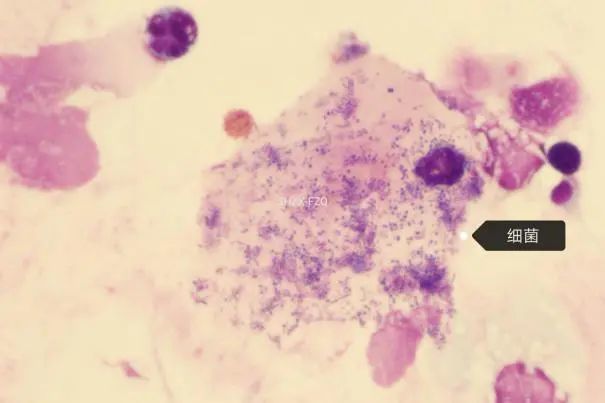

11月2日行支气管镜送检BALF,细胞形态学检验结果:查见成团出现的滋养体,偶见真菌及细菌(考虑耶氏肺孢子菌感染,合并真菌及细菌感染不排除)。瑞-姬氏染色和六胺银染色(1000×)图片及报告分别如下: